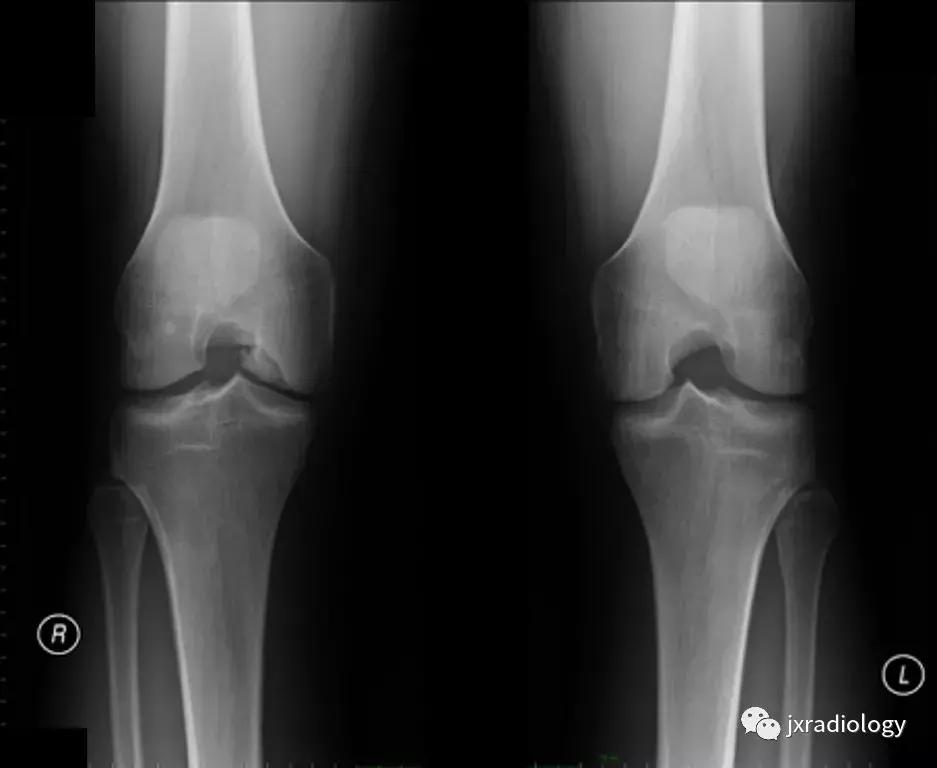

图21:这名患者的炎症性关节炎表现为围绕内侧股 - 胫室侵蚀性改变的骨髓水肿。 它是血管源性骨髓水肿的一个例子(继发于血液和血清传递至骨髓空间毛细血管床)(a,b:冠状T1-WI和PD-FS-WI)。